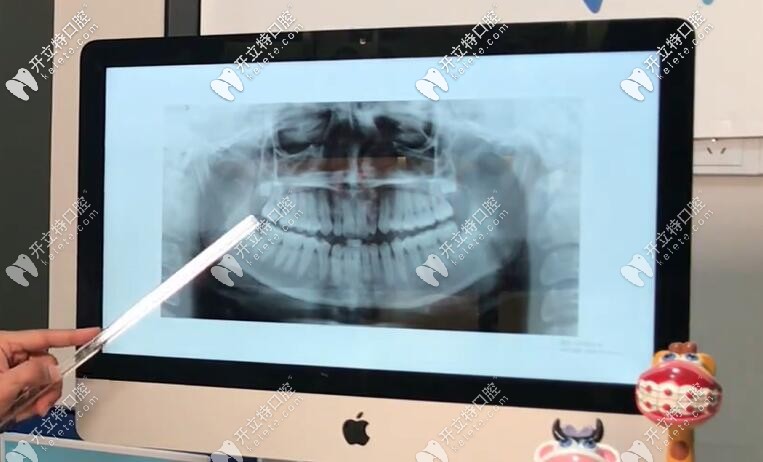

【基本情況】:從圖中(正面)我們可以看出,這個(gè)姑娘的下巴有一點(diǎn)歪,但是她的中線上頜還不錯(cuò),可是出下巴這邊,她的咬合是不對(duì)的,上下頜各有兩顆智齒;

通過(guò)x片和國(guó)貿(mào)口腔的正畸技術(shù)總監(jiān)Dr.Aref安粵夫的分析后,發(fā)現(xiàn)她有點(diǎn)骨性三類(lèi)牙齒畸形,她的下巴有點(diǎn)長(zhǎng),地包天牙齒有骨性問(wèn)題。